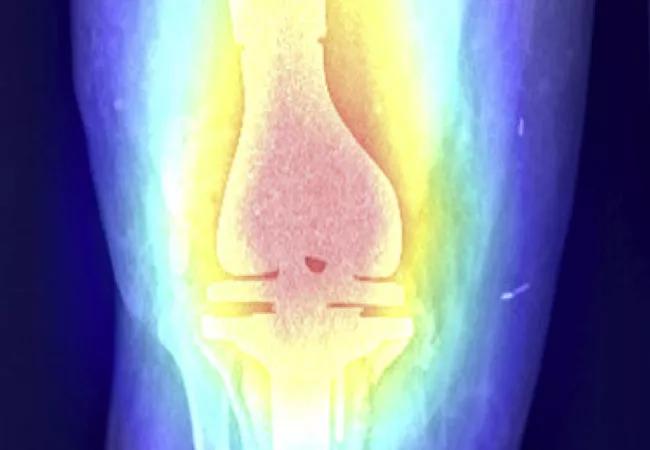

Using artificial intelligence (AI), orthopaedic surgeons at Cleveland Clinic were able to identify the manufacturer and model of an arthroplasty implant with 99% accuracy using plain x-rays alone.

Dr. Ramkumar and members of the Department of Orthopaedic Surgery designed two separate studies to classify knee and hip arthroplasty implants using a deep learning algorithm. Both studies were published in the Journal of Arthroplasty.

The Orthopaedic Machine Learning Lab, part of the Adult Reconstruction Center at Cleveland Clinic, was started by Dr. Ramkumar in collaboration with Viktor Krebs, MD. With Dr. Ramkumar coordinating and leading the study, the team trained, validated and externally tested the algorithm on retrospectively collected hip and knee anterior-posterior (AP) radiographs.

The knee dataset included 682 radiographs (424 patients) with implants from nine different models. The hip dataset included 1972 AP radiographs with 18 different models.

Remarkably, the deep learning algorithm discriminated the knee and hip implant models, respectively, with an area under the receiver-operating characteristic curve of 0.99. These findings didn’t surprise Dr. Ramkumar. Rather, he notes, they underscore the capacity for AI in the field of orthopaedics.